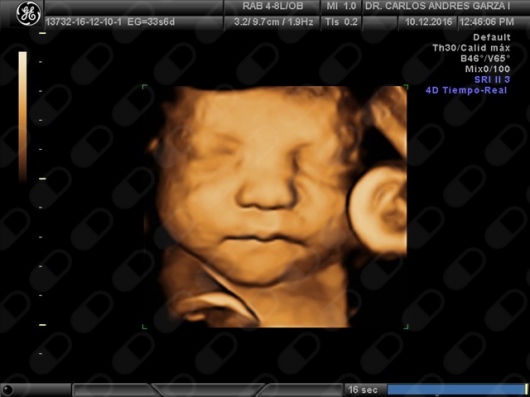

Ultrasonido 4D

!Conoce a tu bebé hoy¡ Se trata de la última tecnología en ecografía o ultrasonido a nivel mundial, que consiste en un procesamiento de reconstrucción digital de imágenes para formar una sola imagen en 4 dimensiones, permitiendo así poder visualizar cualquier estructura tal cual la estuviésemos viendo directamente el rostro de tu bebé, antes de nacer. Con esta nueva generación de tecnología del ultrasonido puedes observar datos mas detallados de su bebé, sus movimientos, gestos, risas, bostezo, etc... tal como si lo tuviera en sus brazos. En el pasado los papas no conocían la cara de su bebe hasta que naciera.